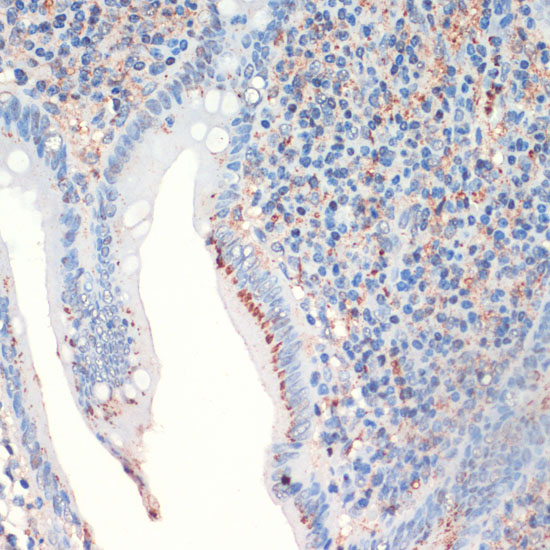

Immunohistochemistry of paraffin-embedded human appendix using SST at dilution of 1:200 (40x lens).